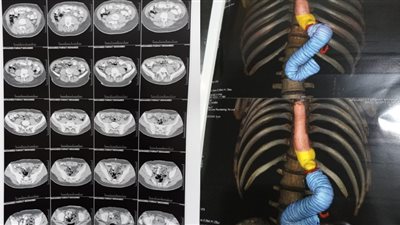

ويلعب الكبد دورًا هامًا في عملية الهضم، حيث ينتج الصفراء التي تساعد في تكسير الدهون، وعندما تتعطل وظائف الكبد، يمكن أن يؤدي ذلك إلى نقص في إنتاج الصفراء، ما يسبب اضطرابات هضمية مثل الإسهال المزمن، لذلك إذا استمر الإسهال عند الطفل لأكثر من أسبوع، يجب مراقبته بعناية بحثًا عن أعراض أخرى قد تشير إلى مشكلات في الكبد، وفيما يلي أعراض مشاكل الكبد عند الأطفال

ويمكن أن تؤدي مشكلات الكبد إلى تضخم في الكبد أو الطحال، ما يظهر كـ تورم في البطن، وقد يصاحبه ألم أو انزعاج، خاصة في الجانب الأيمن العلوي.